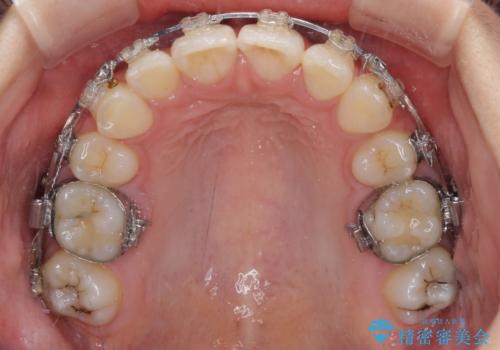

治療途中で転院 抜歯矯正の仕上げ治療

- 地元で抜歯治療を行っている途中、東京へ転職したため治療を継続して欲しいとのことで来院された患者様です。

出っ歯を抜歯矯正にて治療をしていらっしゃいましたが、抜歯スペースが少し残っていたため、閉じて歯列を仕上げていくこととしました。